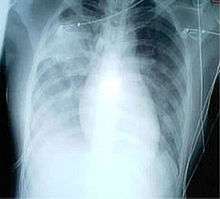

For a case to be considered probable, a chest X-ray must be positive for atypical pneumonia or respiratory distress syndrome.

When it comes to the chest X-ray the appearance of SARS is not always uniform but generally appears as an abnormality with patchy infiltrates.[5]